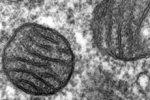

Болезни сердца могут уйти в прошлое благодаря клеточным технологиям

Стволовые клетки применяют для лечения больных с различными заболеваниями, в том числе и с кардиологическими проблемами. "Эффективность применения с...